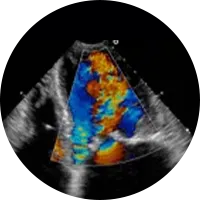

A Ecografia é um método de estudo e diagnóstico que permite, devido à emissão de ondas sonoras ou ultra-sons, examinar diversas áreas do corpo e órgãos e confirmar um diagnóstico clínico. Pode, portanto, ser usada para fins muito diversos como a observação ao pormenor do fígado, a vesícula biliar, rins, baço, tiróide, próstata, artérias e veias (Ecodoppler), entre outros. O exame de ecografia não causa nenhuma dor.

Existem vários tipos de preparação para os diferentes tipos de ecografia.